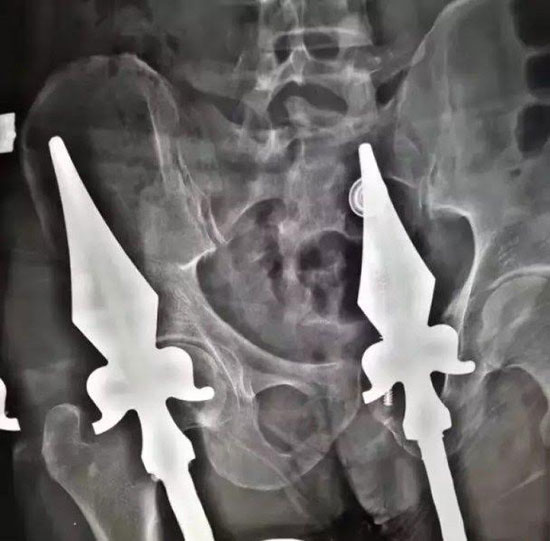

เมื่อวันที่ 16 มีนาคม 2560 เว็บไซต์เมโทร รายงานข่าวชวนหวาดเสียวจากประเทศจีน ระบุว่า ชายรายหนึ่งเกิดอุบัติเหตุพลัดตกลงมากระแทกกับรั้วเหล็กอย่างแรง ถ้ารั้วดังกล่าวเป็นรั้วขอบเรียบธรรมดา ชายคนนี้ก็อาจจะไม่ได้รับบาดเจ็บมากมายอะไร แต่เคราะห์ร้ายตรงที่รั้วดังกล่าวเป็นรั้วเหล็กแหลม จึงถูกเสียบแทงทะลุเข้าตรงส่วนบั้นท้าย และตัวติดแหง็กอยู่บนนั้นอย่างเจ็บปวดทรมาน

เหตุการณ์ดังกล่าวเกิดขึ้นที่บ้านหลังหนึ่งในเมืองซีอาน มณฑลส่านซี ทางตอนเหนือของประเทศจีน โดยชายผู้ประสบเหตุคือช่างแอร์ที่มาทำหน้าที่ติดตั้งแอร์อยู่บริเวณชั้นสองของบ้าน ซึ่งในระหว่างปฏิบัติงานเกิดพลาดท่า หล่นลงมาโดนรั้วเหล็กเสียบดังกล่าว

หลังจากนั้น ศัลยแพทย์ได้ทำการผ่าตัดนำเอารั้วเหล็กแหลมออกมาได้สำเร็จ โดยตอนนี้ช่างแอร์รายนี้อาการปลอดภัยแล้ว แต่ทั้งนี้จะต้องนอนพักรักษาตัวที่โรงพยาบาลเพื่อให้แพทย์ดูอาการต่อไป